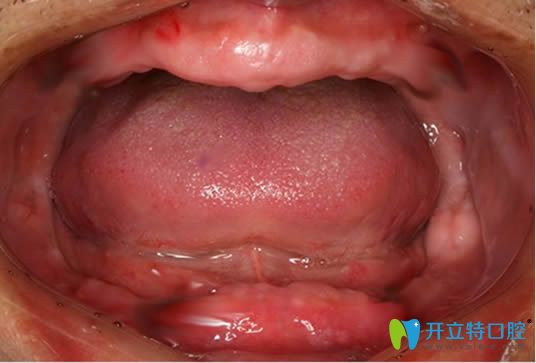

探討全口吸附性義齒技術(shù)原理并附bps生物吸附性義齒的價格

全口吸附性義齒主要是根據(jù)個人牙槽骨條件,由醫(yī)生精細(xì)取模和后期技師的制作,才能使義齒達(dá)到充分的邊緣封閉,和牙床產(chǎn)生牢固的吸附力,下文就有講解,并附bps生物吸附性義齒的收費(fèi)價格